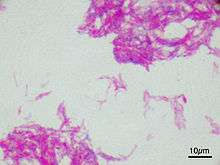

Pathological classification

90% of bladder cancers are transitional cell carcinoma. The other 10% are squamous cell carcinoma, adenocarcinoma, sarcoma, small cell carcinoma, and secondary deposits from cancers elsewhere in the body.

Carcinoma in situ (CIS) invariably consists of cytologically high-grade tumour cells.